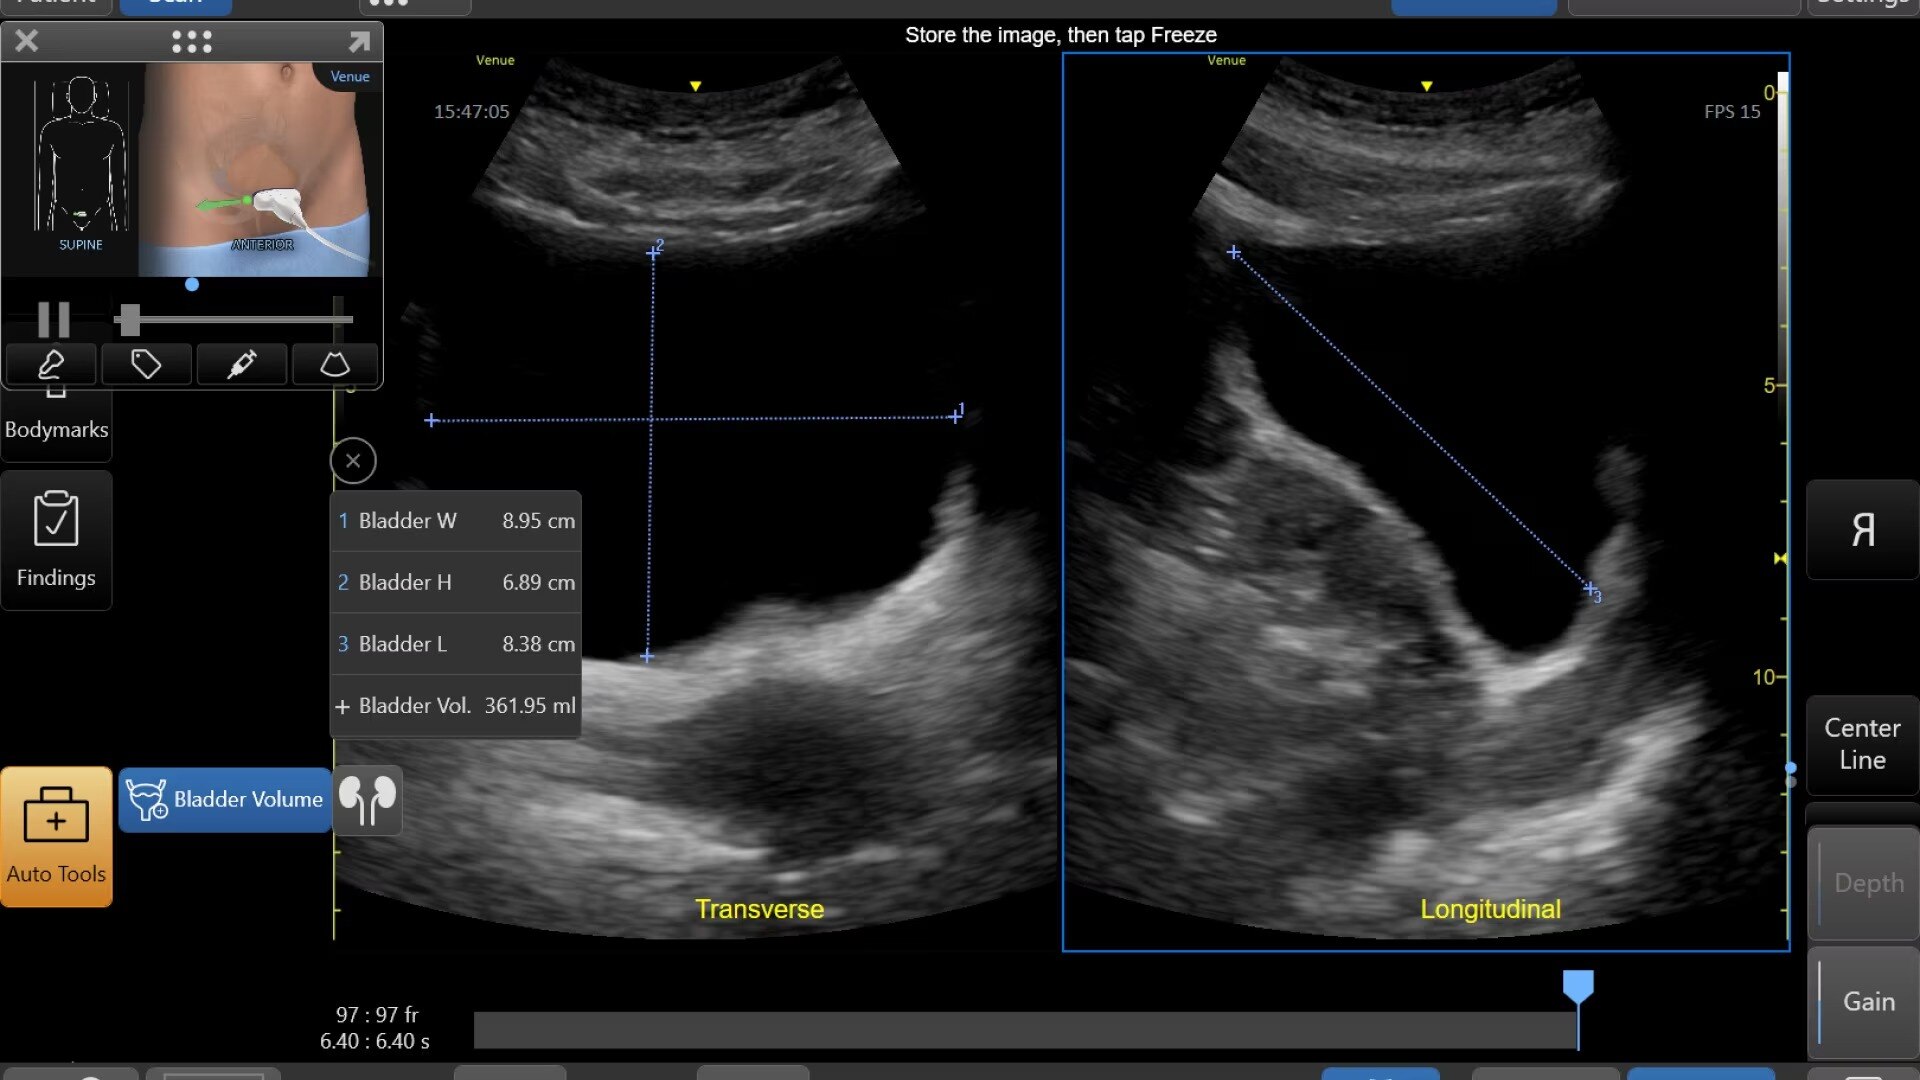

Auto Bladder Volume

Quick and easy measurements

AI-enabled tool provides rapid and easy urinary bladder volume measurements, saving clinicians valuable time and enhancing clinical accuracy. It measures bladder dimensions and calculates the bladder volume from two views: transverse and longitudinal.